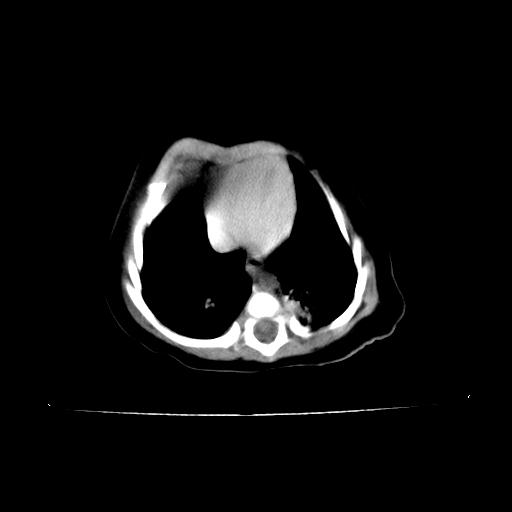

以下是引用影像之路在2009-5-8 15:46:00的发言:[br]1)胸廓畸形。2)考虑两肺感染性病变,并右肺上中叶肺不张;建议抗炎治疗后复查。3)胸腺肥大。4)前上中纵隔占位性病变待排;建议追踪复查。

以下是引用随光逐影在2009-5-8 8:33:00的发言:[br]1)胸廓畸形。2)考虑两肺感染性病变,并右肺上中叶肺不张;建议抗炎治疗后复查。3)胸腺肥大。4)前上中纵隔占位性病变待排;建议追踪复查。

以下是引用余辉在2009-5-8 8:44:00的发言:[br]鸡胸,胸腺肥大,双肺感染性病变,结合病史支原体肺炎可能性大